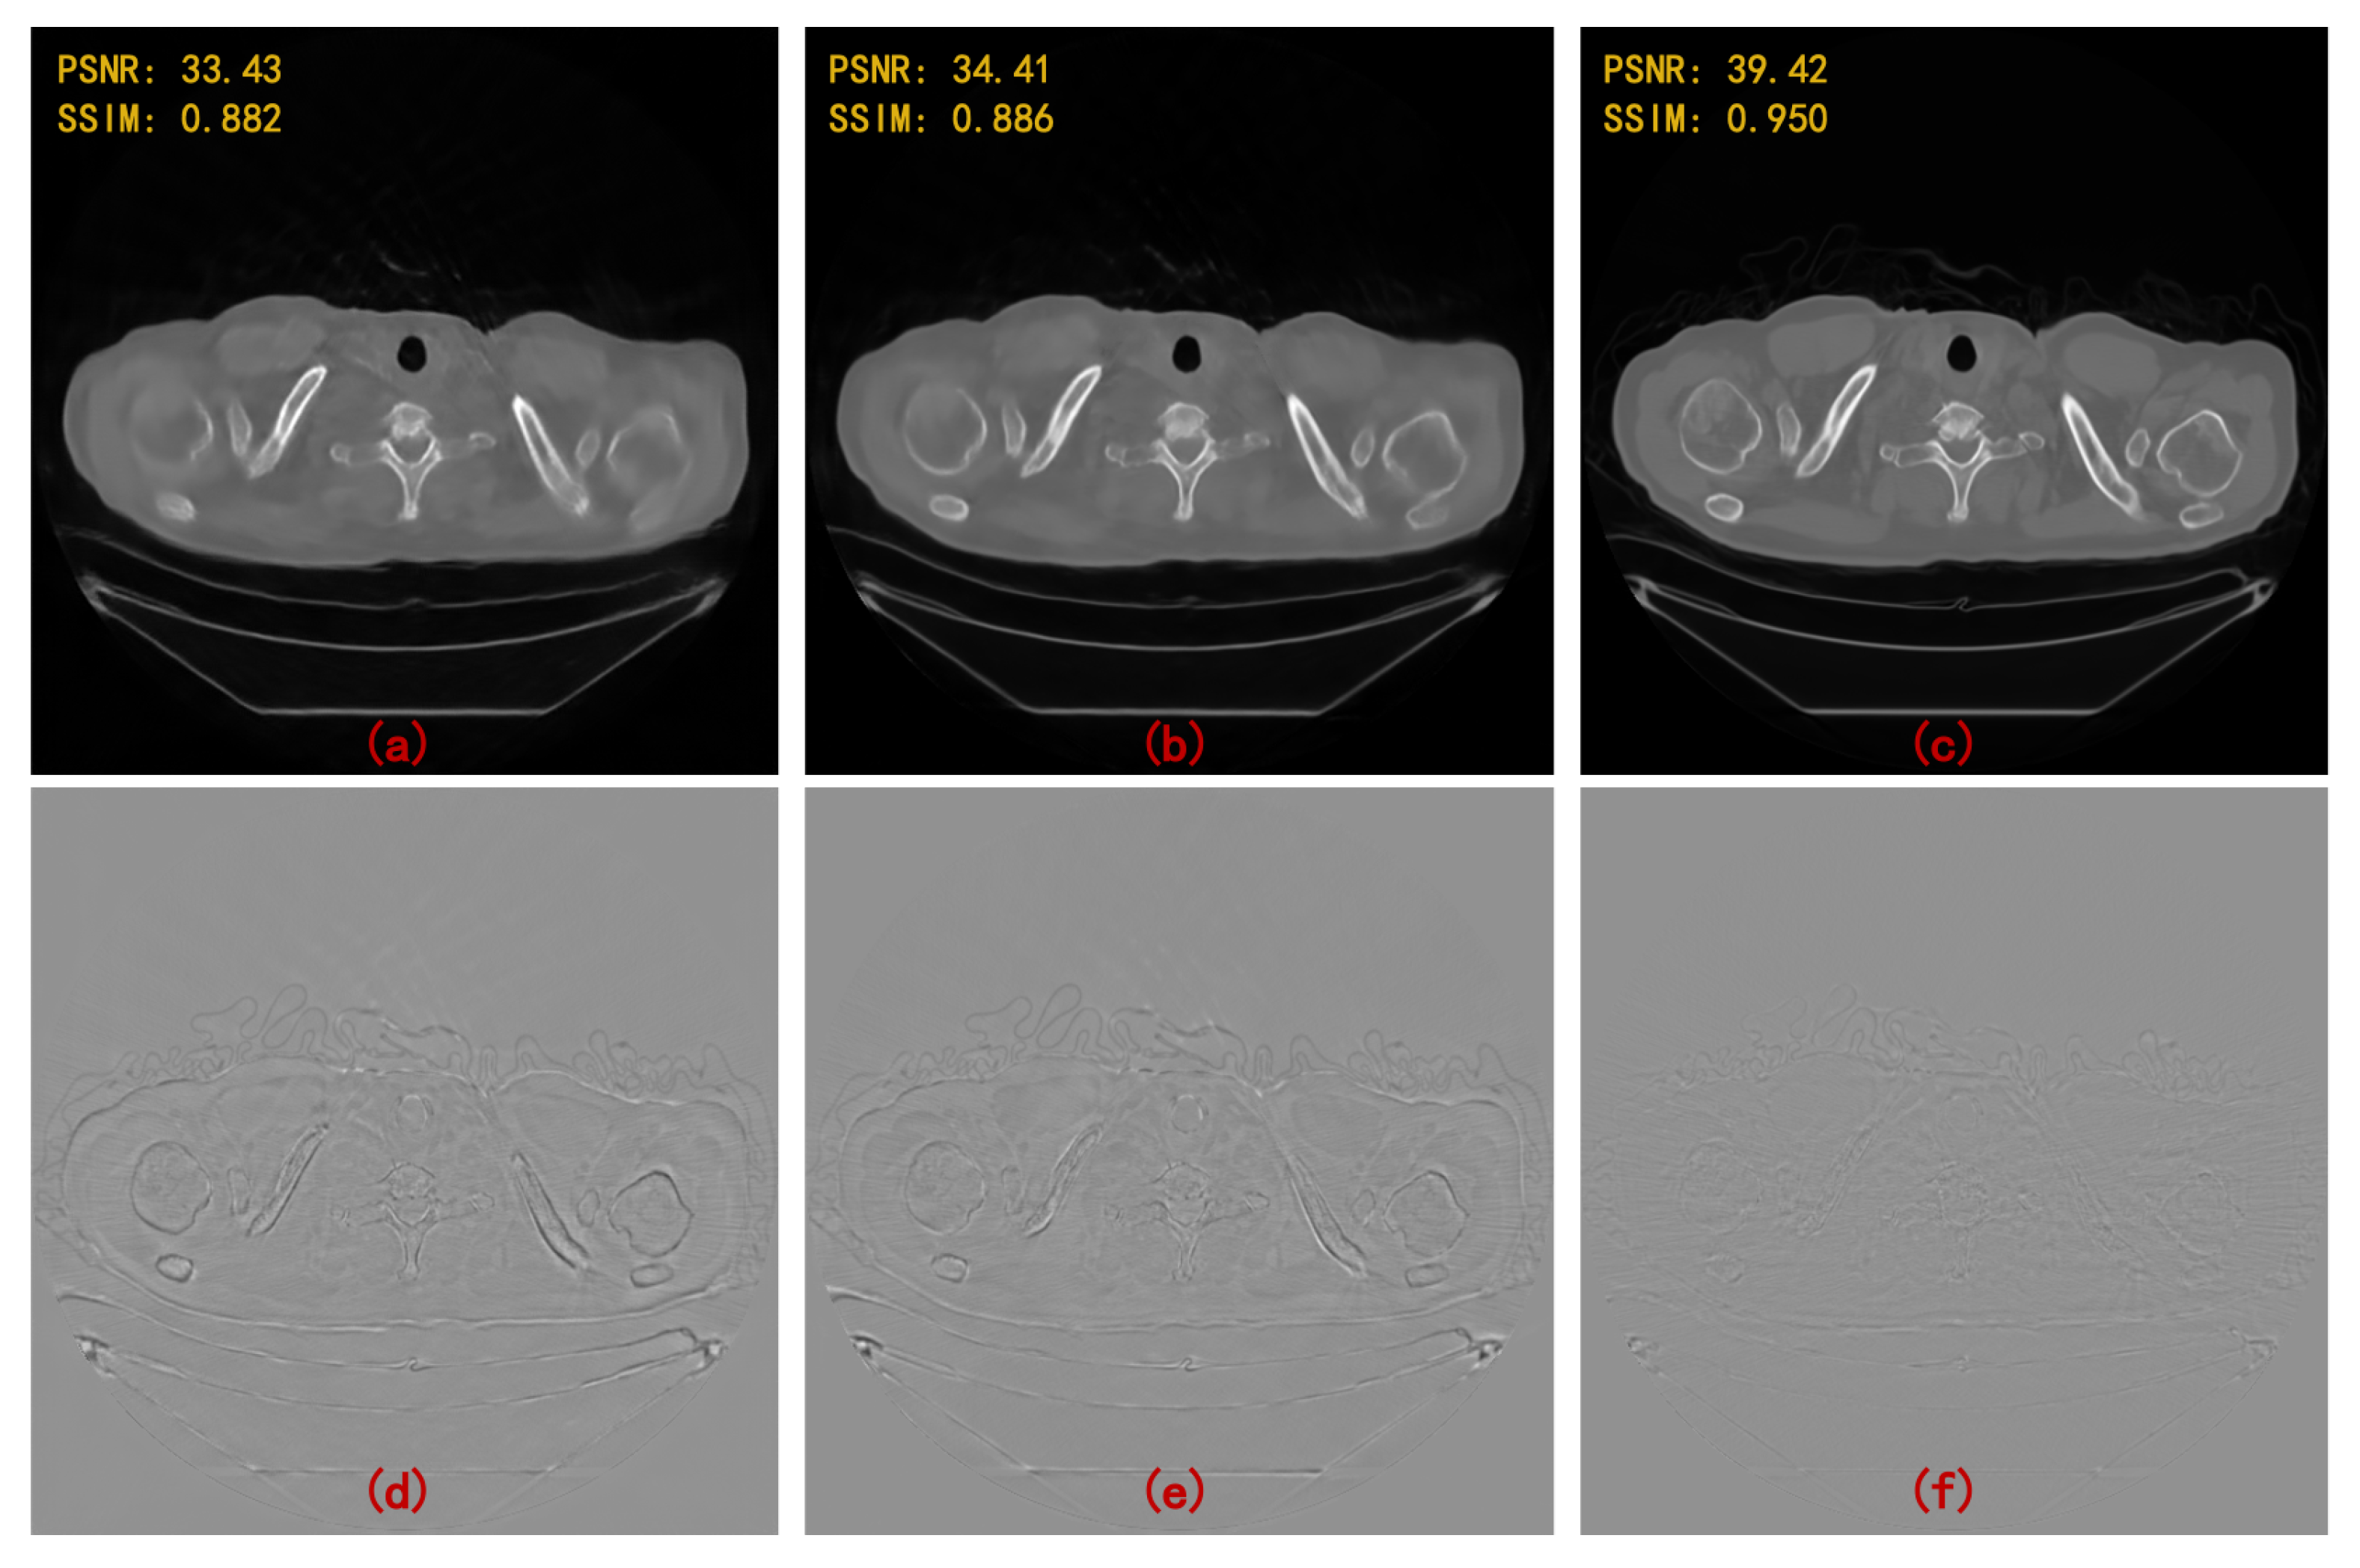

| FBP | Linear + FBP | SART-TV | Proposed | |

|---|---|---|---|---|

| 120 views | 28.725 | 30.241 | 34.405 | 41.049 |

| (3-degree) | 0.558 | 0.802 | 0.903 | 0.958 |

| 90 views | 26.702 | 28.475 | 32.190 | 40.204 |

| (4-degree) | 0.483 | 0.765 | 0.862 | 0.956 |

| 60 views | 23.259 | 26.279 | 30.085 | 37.718 |

| (6-degree) | 0.391 | 0.698 | 0.810 | 0.938 |

| 30 views | 19.496 | 23.399 | 26.711 | 33.100 |

| (12-degree) | 0.280 | 0.624 | 0.726 | 0.891 |